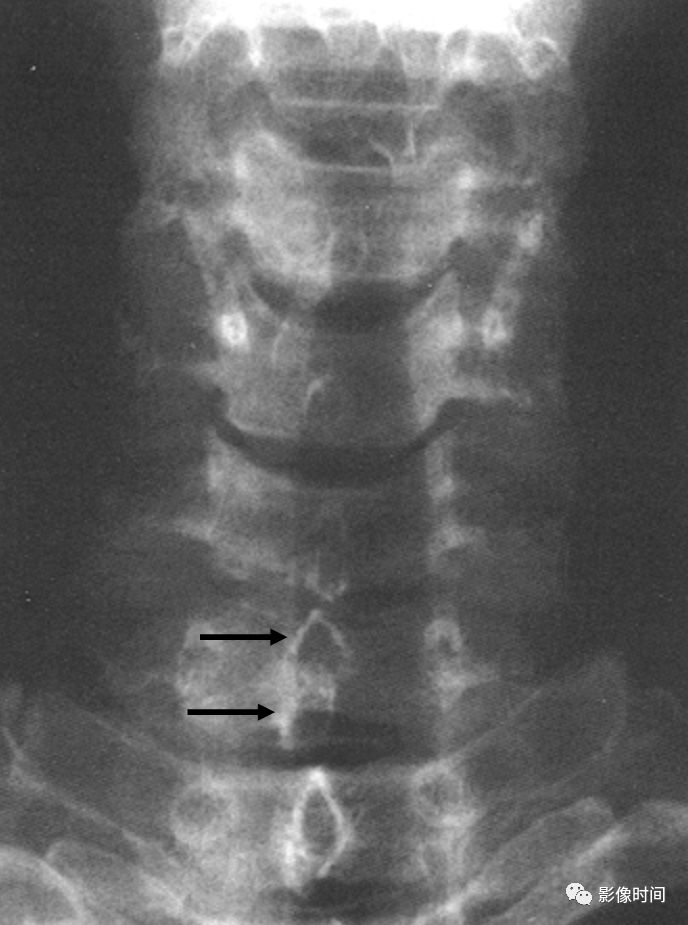

匕首征,或译为短剑征(Dagger sign)

匕首征是指由于棘间韧带骨化,导致在正位 X 线片上呈现垂直的一条硬化带(白箭),形似一把短而窄的匕首而得名。此征象也主要用于描述强直性脊柱炎。

典型病例

强直性脊柱炎。正位 X 线片示棘间及棘上韧带骨化形成匕首征(黄箭)。另可见双侧骶髂关节骨性融合,双髋关节间隙均匀性狭窄。